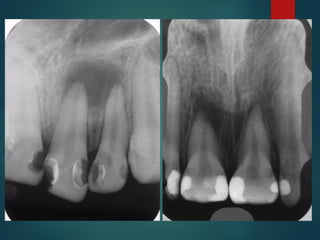

Clasificación Radiográfica

De Las Caries

Incipiente de esmalte

De esmalte

Dentinaria superficial

Dentinaria profunda

Sobreproyectada en cámara pulpar

Penetrante